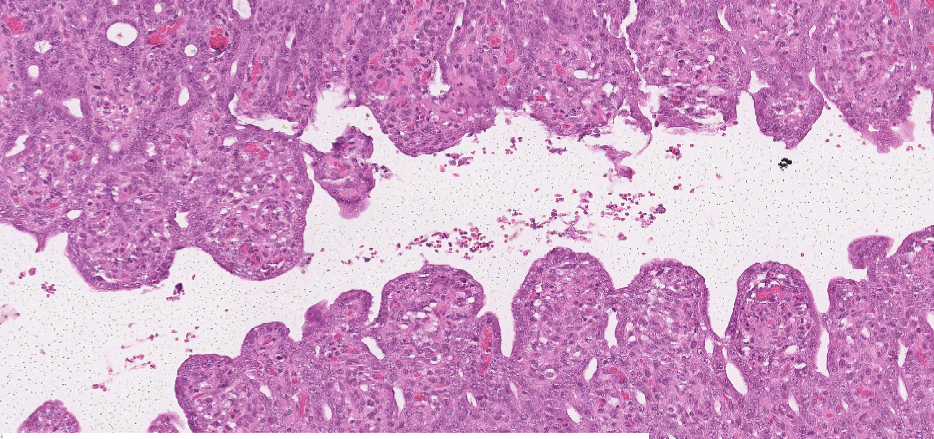

Morphologic Dx? Pathogenesis?

• SI; villous atrophy/blunting and fusion (crypts are intact)

1. Viral infection of villar tip epithelium

2. necrosis of epithelium at tips

3. villous atrophy

4. healing by adjacent epithelium and cy crypt hyperplasia

5. villous fusion